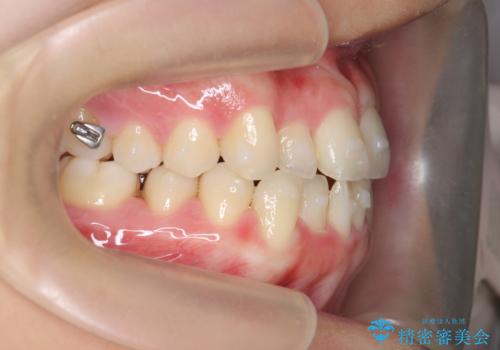

マウスピース矯正で前歯のガタつきを改善

- 上下の前歯のガタつきの改善を求めて、矯正治療を希望され来院されました。

矯正検査の結果、マウスピース矯正システム インビザラインの適応であることからワイヤーを用いず矯正治療を進めることとしました。

1日20時間以上の使用時間をきっちりと守っていただけたため、良好な治療結果、歯並びを手に入れることができました。